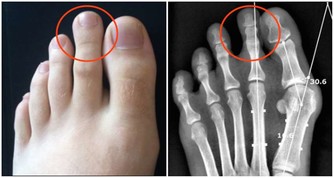

(1)下腹部不適初期偶有下腹部不適或一側下腹有墜疼感。

(2) 腹部膨脹感,由於腫瘤生長迅速短期內可有腹脹,腹部腫塊及腹水。腫瘤小的只有在盆腔檢查時才能發現,腫塊逐漸長大超出盆腔時,腹部可以觸到腫塊。

(3) 壓迫症狀,當腫瘤向周圍組織浸潤或壓迫神經時,可引起腹痛、腰痛或坐骨神經痛,若壓迫盆腔靜脈,可出現下肢浮腫;巨大的腫瘤可壓迫膀胱,有尿頻、排尿難、尿瀦留;壓迫直腸則大便困難;壓迫胃腸道便有消化道症狀;壓迫膈肌可發生呼吸困難,不能平臥。